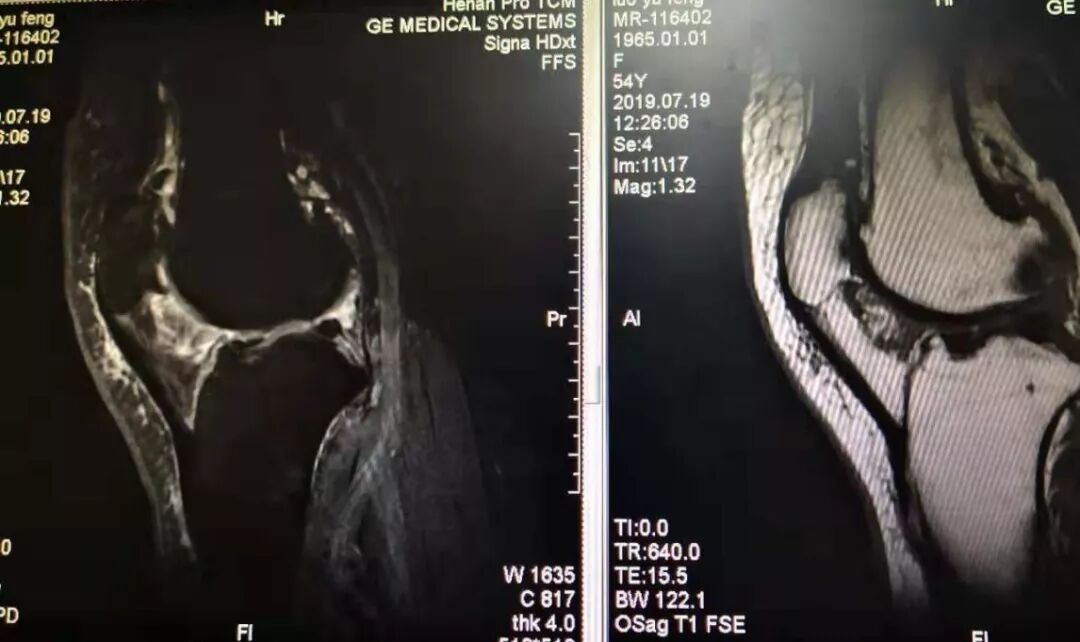

膝关节骨关节炎的磁共振影像

一例弧刃针标准疗法治膝关节骨关节炎的典型病例